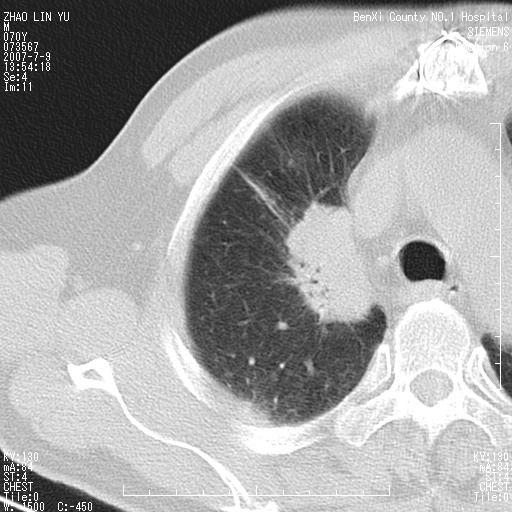

以下是引用王靖旗在2007-7-10 17:12:00的发言:[br] 男、70、咳嗽两个月,半年前换瓣手术,胸片未见异常,于昨天行x片发现右肺上野大片影,行ct扫描,这里是减薄图像,余肺正常。明天晚上会有增强扫描片,到时我会上传。[br][br] 冠状位请大家细看,应该是有意义的,[br][br] 请大家先看平扫发表意见。[br][br]

以下是引用zhangzhongshou在2007-7-10 21:43:00的发言:[br]右肺上叶周围型肺癌,以孤立型细支气管肺泡癌可能性大。